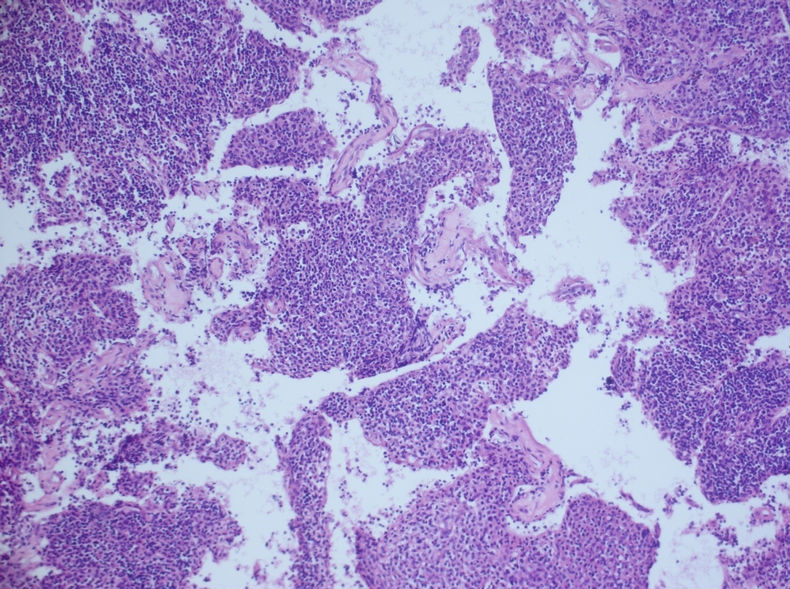

发现左侧胸壁肋间肿块1月,约3.5×4 。病例分享——男性,55岁,左胸壁肋间肿块图1

术后病理示:胸腺瘤(B3型为主)

肋间肿块切除的标本有的,形态和细胞腊块一致,属于胸腺瘤B2+B3型。

根据腊块及免疫组化结果,我诊断了

(左胸壁)转移性胸腺瘤(B2型)

建议检查纵隔。

随访,纵隔发现一3.5×3cm肿块,术后病理示:胸腺瘤(B3型为主)

我当时就让病人等两天,等我把细胞腊块的结果出来后告诉他。

细胞腊块图片如下:

的确这例涂片诊断非常困难,我刚看到涂片的时候,也是一团雾水,我看到淋巴细胞及组织细胞样细胞两种成分。

当时考虑:1、肉芽肿性炎,2、转移性鼻咽部的非角化性未分化癌、3、淋巴结增生、4、转移性胸腺瘤,5、软组织肿瘤6、……